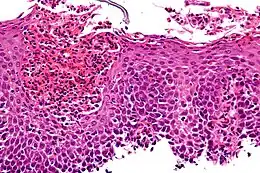

Œsophagite à éosinophiles, coloration à l'hématoxyline et à l'éosine.

Le diagnostic final peut tout de même être établi grâce au comptage des polynucléaires éosinophiles grâce à des biopsies œsophagiennes. La biopsie est demandée si le médecin suspecte une œsophagite ou une maladie voisine. Le diagnostic repose principalement sur la présence d’une infiltration de la muqueuse œsophagienne supérieure à 15 éosinophiles par champ de vision microscopique (x 40)[7]. Plusieurs biopsies peuvent se révéler nécessaires.